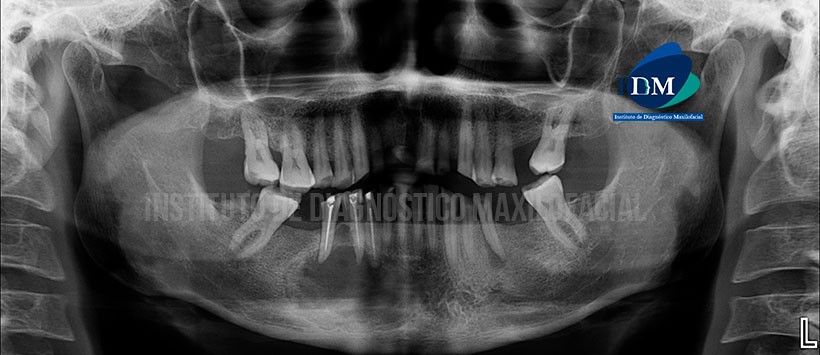

A la evaluación de la radiografía panorámica se aprecia una imagen radiolúcida de limites parcialmente definidos, localizado en zona parasinfisiaria y parte del cuerpo mandibular de lado derecho, también se evidencia un leve aumento de la densidad ósea circundante, borramiento de las corticales del conducto dentario inferior, agujero mentoniano y lamina de dura de las piezas 43, 44 y 45, las cuales a su vez presentan material de obturación de conductos. (Figura 1)